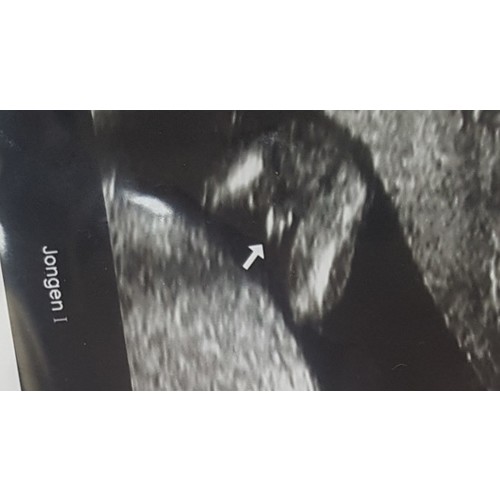

Dit is sowieso een jongen 🤪

Toen ik precies 15 weken was dacht de gynaecoloog ook een jongen te zien. Ze gaf aan dat het wel vroeg was en dat ze er niet zeker van was. Heb daarom met 17 weken nog een pretecho laten maken en zie de bijgevoegde foto. Kon echt niet missen 😅. Op bijna alle echo's daarna moest die altijd even laten zien dat hij nog steeds een jongen is 🙈.